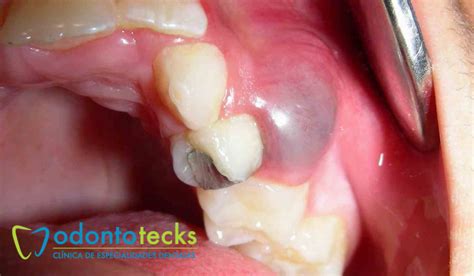

Diferentes tipos de quistes dentales.